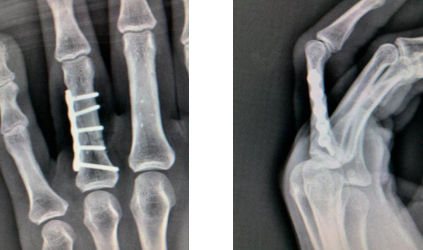

术后即刻骨折内固定情况

爱美之心人皆有之,魏女士既想有坚强牢固的固定骨折、早期进行功能锻炼、恢复良好的功能,又很担心如果手术会留下难看的疤痕。熊医生表示,请魏女士放心,一般来讲此类手术通常采用的是背侧切口,瘢痕外露明显,对美观影响较大。而我们现在采用手指侧方切口,钢板放置在指骨侧方,手术瘢痕位置相对隐蔽,同时骨折固定的牢固性亦非常好,相比背侧钢板,本术式对肌腱的影响更小,此术式不仅利于早期的功能锻炼,而且手术瘢痕位置隐蔽,外形美观。这下魏女士放心了。